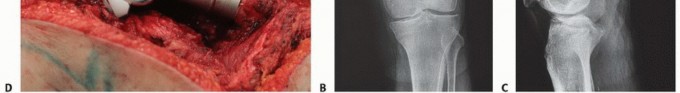

استئصال الورم وإعادة البناء (Resection and Reconstruction):

- الوصف: يتم إزالة الجزء المصاب من عظم الفخذ الذي يحتوي على الورم، ثم يتم إعادة بناء العظم باستخدام غرسات معدنية خاصة (مثل الأطراف الاصطناعية المخصصة للأورام) أو طعوم عظمية.

- الاستخدام: للحالات التي يكون فيها الورم كبيرًا أو يدمر جزءًا كبيرًا من العظم، خاصة إذا كان يمكن تحقيق استئصال كامل للورم.

- ميزاته: يوفر استقرارًا طويل الأمد ويقلل من خطر عودة الورم في نفس الموقع.

توسيع العظم (Curettage) مع تعبئة الإسمنت العظمي (Bone Cement):

- الوصف: يتم إزالة الأنسجة السرطانية من داخل العظم باستخدام أداة خاصة، ثم يتم ملء التجويف الناتج بإسمنت عظمي لتقوية العظم وتثبيته.

- الاستخدام: للآفات الصغيرة المعزولة التي لا تهدد بكسر كبير.

- ميزاته: إجراء أقل توغلاً، يساعد على تقوية العظم وتخفيف الألم.